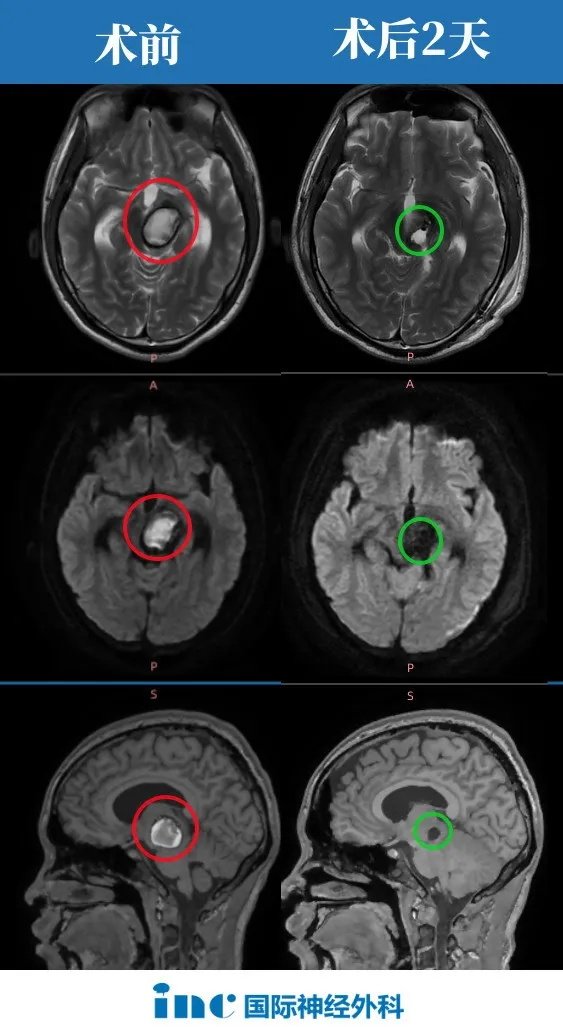

▼在国内手术团队的配合下,巴教授全程主刀手术

▼据术中神经电生理医生的反馈——小林的病灶切完之后运动神经的反应明显好转。

”当时教授出来之后,他说非常棒。我当时哭的都不行了。作为一个母亲,感觉太好了,没想到能有这么好的结果。孩子出来之后,我说你认不认识我,他说认识妈妈,脚也能动。“看着孩子仅仅术后就恢复这么快,小林母亲格外感恩。

术前坐着轮椅来到医院的他,术后第1天ICU查房时,状态良好,能够正常交流,双腿能动、能曲,手部也有力量。

术后第3天时,小林母亲再次和我们分享了孩子的最近情况。“原先他生病的时候喝水都漏,现在吃饭喝水啥问题都没有。所以巴教授的技术真的非常厉害,所以找到他我们也算是挺幸运的,真是有好多人真找不着。原来右边麻没有劲,现在右边也有力量了。说话也清楚了,没有大舌头了。现在状态明显比手术之前好,是非常好的结果。现在说话也清楚了,能卷翘舌了,数字也能说清楚,10和4。”